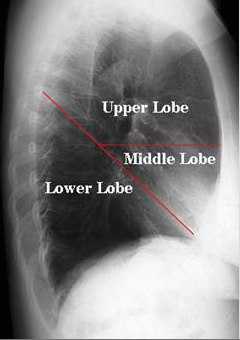

Представлена рентгенограмма правого лёгкого в боковой проекции с указанием топографии междолевых щелей.

Лёгкие располагаются в грудной клетке, занимая большую ее часть, и отделены друг от друга средостением. Размеры лёгких неодинаковые вследствие более высокого положения правого купола диафрагмы и положения сердца, смещенного влево.

В каждом лёгком различают доли, разделенные глубокими щелями. Правое лёгкое состоит из трёх долей, левое — из двух. На правую верхнюю долю приходится 20% лёгочной ткани, на среднюю — 8%, правую нижнюю — 25%, левую верхнюю — 23%, левую нижнюю — 24%.

Главные междолевые щели проецируются справа и слева одинаково — от уровня остистого отростка 3 грудного позвонка они направляются косо вниз и вперед и пересекают 6 ребро у места перехода его костной части в хрящевую.

Дополнительная междолевая щель правого лёгкого проецируется на грудную клетку по ходу 4 ребра от средней подмышечной линии до грудины.

На рисунке обозначены: Upper Lobe — верхняя доля, Middle Lobe — средняя доля, Lower Lobe — нижняя доля